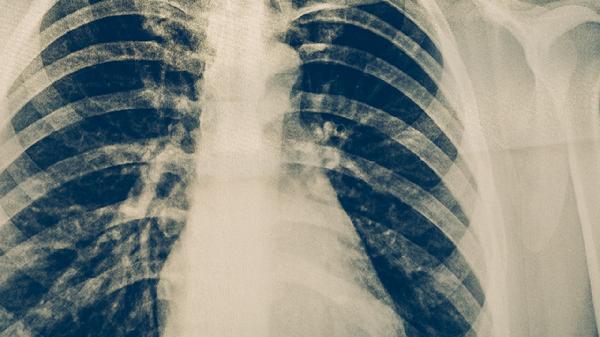

胸部X線或CT檢查能發(fā)現(xiàn)肺結核的典型病變,如上肺野浸潤影、空洞形成、纖維鈣化灶等。影像學檢查對無癥狀的早期病變有較高檢出率,但缺乏特異性,需與肺炎、肺癌等疾病鑒別。對于痰檢陰性的疑似患者,影像學檢查可為診斷提供重要依據(jù),同時能評估病變范圍和治療效果。